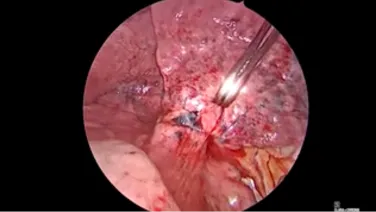

Thorascopic Lobectomy - Staple and Divide the Lobar Bronchus